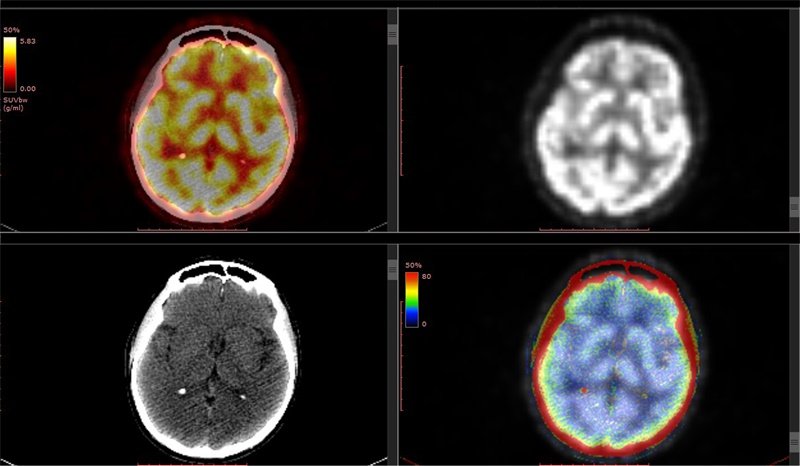

MRI:斜坡占位的“照妖镜”

在斜坡病变检查中,MRI凭借卓越的软组织分辨力成为首选:

- 无骨伪影干扰:清晰显示病变与神经血管关系

- 多序列联合:揭示不同组织特性

高级序列的精准洞察:

- DWI序列:2023年《Neuro-Oncology》研究证实,脊索瘤平均ADC值(0.75×10⁻³mm²/s)显著低于脑膜瘤(1.12×10⁻³mm²/s),这为鉴别提供了量化依据